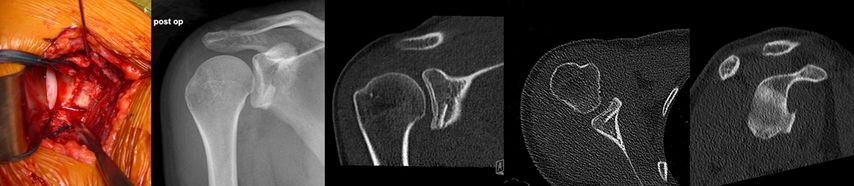

Abb. 3: Erneute Luxation durch neuerliches adäquates Trauma ohne relevanten Knochendefekt, keine generalisierte Hyperlaxizität

Zusätzlich zur Kapsel-Labrum-Refixation wird in zunehmendem Maße eine Remplissage (unanatomische Kapsulotenodese der Infraspinatussehne) empfohlen, dies insbesondere bei Revisionseingriffen, bei sehr sportlichen Patienten, besonders Kontaktsportlern und Patienten mit hohem funktionellem Anspruch und einer hohen Rezidivgefahr57,58 (Abb. 4a, 4b). Ursprünglich für Patienten mit großen Hill-Sachs-Defekten empfohlen („off-track“ Läsionen), ist in jüngerer Zeit eine deutlich großzügigere Indikationsstellung zur Remplissage auch bei „on-track“ Läsionen festzustellen.59 Für arthroskopische Bankartoperationen mit zusätzlicher Remplissage sind deutlich geringere Versagerraten und bessere Sportfähigkeit beschrieben.60 Die früher beklagte signifikante Einschränkung der Beweglichkeit nach einer Remplissage konnte in der neueren Literatur nicht bestätigt werden.61

Abb. 4a, b: Zusätzlich zur Kapsel-Labrum-Refixation wird in zunehmendem Maße eine Remplissage empfohlen, dies insbesondere bei Revisionseingriffen, bei sehr sportlichen Patienten mit hohem funktionellem Anspruch und einer hohen Rezidivgefahr